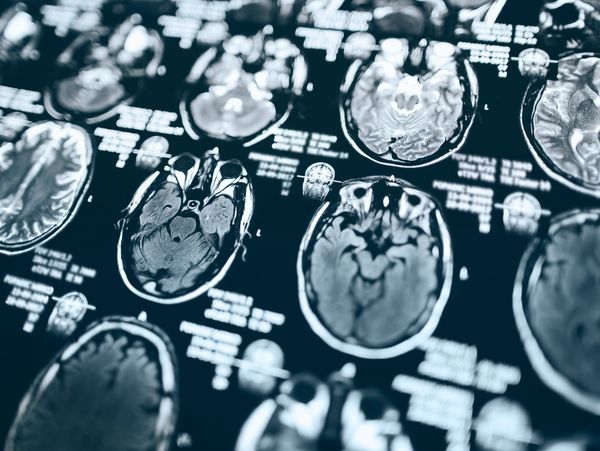

Brain scans (FDG PET) used in the diagnosis of Alzheimer's disease. The scans show a healthy brain, a brain with mild cognitive impairment and a brain with Alzheimer's.